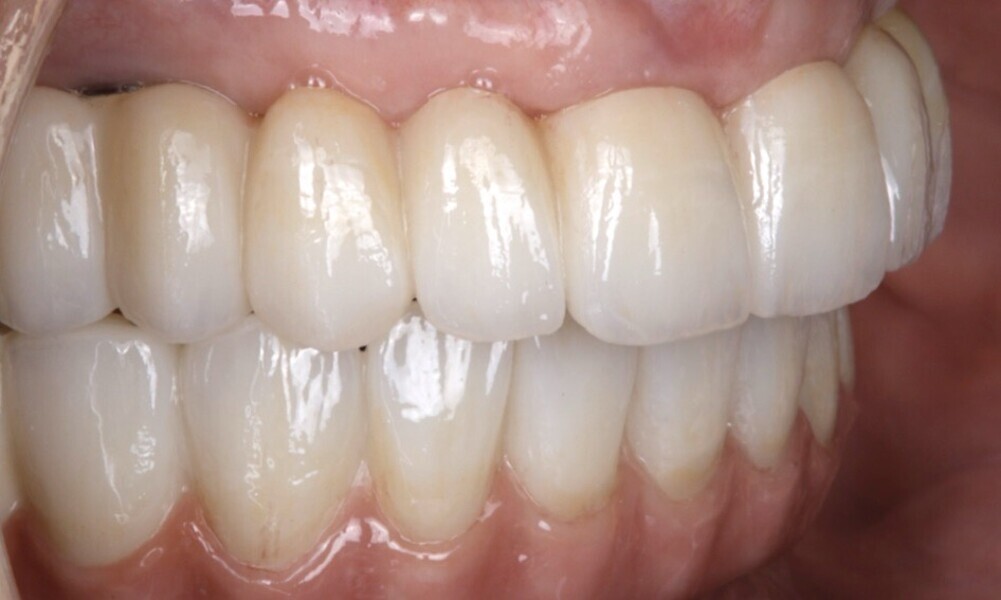

The soft tissue was in good condition, and the definitive restorations were placed (Figs. 76 & 77). After placing the definitive restorations, oral hygiene instructions were given to ensure proper care and prevent complications. Additionally, the occlusion was carefully checked and adjusted as needed (Figs. 78–83).

Figs. 78–82: The definitive restorations were placed, and occlusal adjustments were performed.